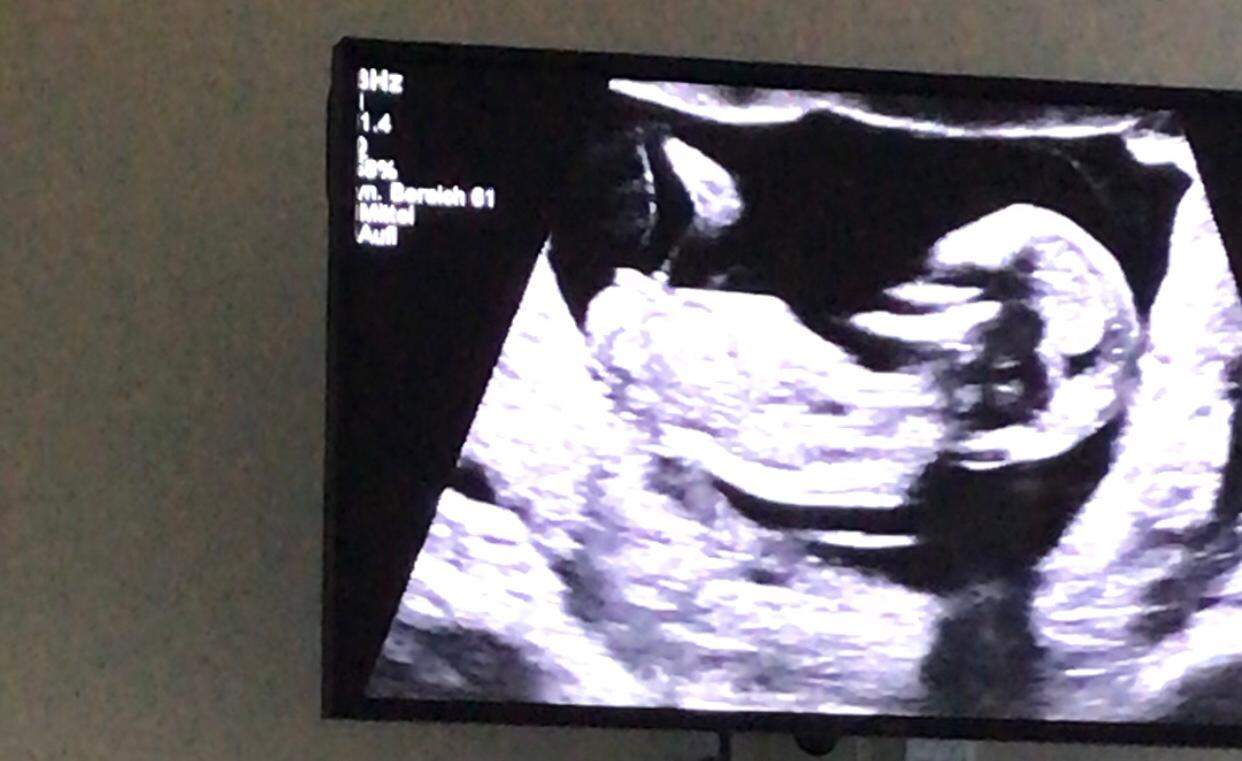

Ultraschall geschlecht junge falsch. Viele Eltern interessiert es brennend das Geschlecht ihres Kindes schon vor der Geburt zu erfahren. Nub theorie junge falsch - riesenauswahl an markenqualitä. Bei mir sagte der Harmony-Test dass es ein Junge wird.

Auch die Größe des Uterus Narben im Bauchbereich die Position des Babys und andere Faktoren spielen eine Rolle. Es folgte einer in der 20. Außerdem kann der Junge die Beine kreuzen und der Ultraschall ist für sein Geschlecht nicht sichtbar.

Ramzi methode - mamacommunity. Wie gut ihr euer Baby auf dem Ausdruck erkennen könnt ist unter anderem von der Lage des Kindes der Erfahrung des Arztes und von der Qualität des Geräts abhängig. Schädel Theorie Geschlecht schädel-theorie ist nicht die.

SSW blickte die Ärztin lange auf das Ultraschall-Gerät als Svenja fragte wie es ihrem Sohn ginge. Geschlecht unter dem Ultraschall erkennen. Kann die Bestimmung des Geschlechts per Ultraschall falsch sein.

Mich hätte es jetzt auch gewundert wenn bei jemandem das durch den praenatest bestimmte Geschlecht falsch gewesen wäre. SSW noch etwas schwierig die Geschlechter. Natürlich bin ich glücklich wenn das Baby gesund zur Welt kommtGeschlecht da echt zweitrangig aber mich interessiert halt ob es doch trotz 3D-Ultraschall schon mal zur Fehldiagnose bzgl.

Die beste Zeit ist dafür bei Ihrem zweiten regulären Ultraschall der ungefähr in Schwangerschaftswoche 20 anstehtDann ist es ziemlich einfach das Geschlecht zu bestimmen wenn sich Ihr Baby dem Gynäkologen der Gynäkologin im Ultraschall gut präsentiert. Ramzi methode plazenta über 80 neue produkte zum.